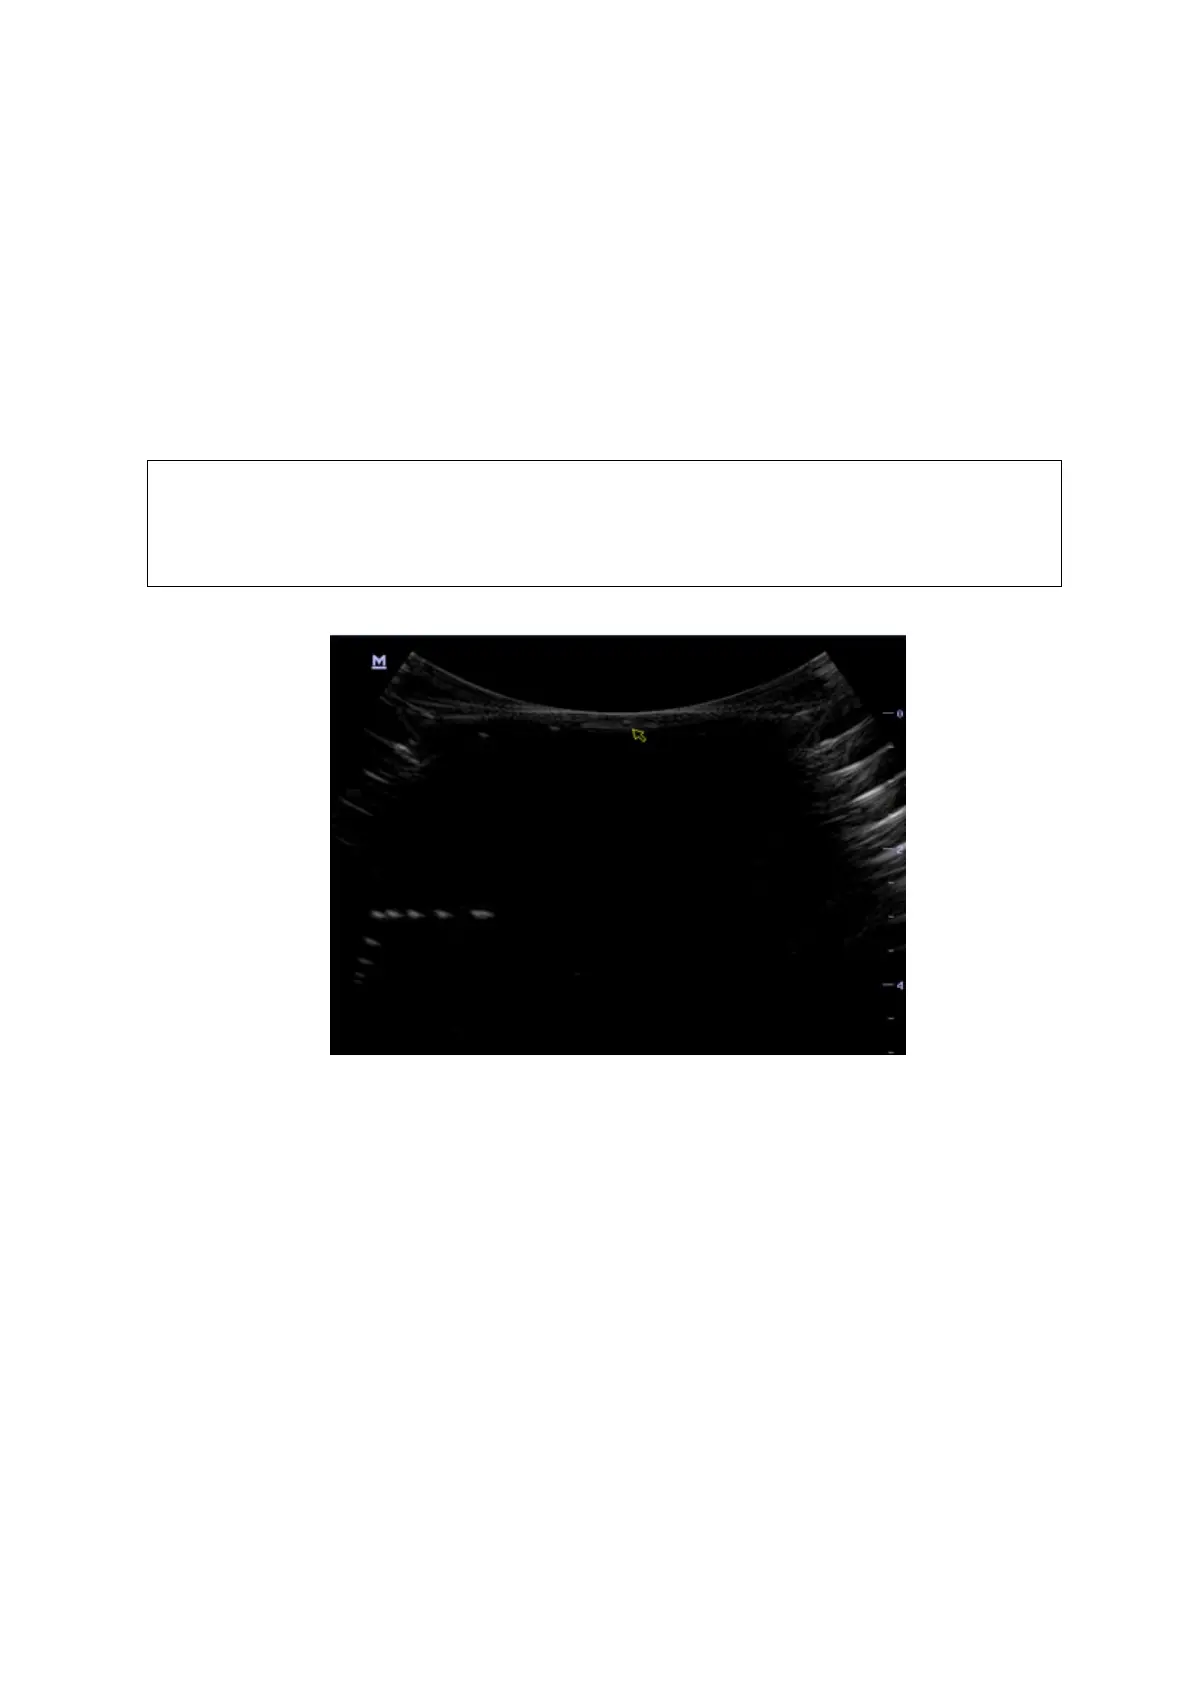

5.5.2.4 Blackout Area

Test Step:

1. Cover the scan surface of the phantom with water or couple gel, gently contact the probe with

the scan surface

2. Adjust the depth at a lower value, and set the focus at the nearest place to the scan surface.

3. Decrease the value of parameters like AP, Gain until the background noise just can be seen.

4. Record the smallest depth of the target that can be seen clearly, that value is the blackout area

value.

NOTE:

1.

When using a linear probe, please completely contact the probe with the

scan surface, no side clearance is allowed.

2.

For convex probe, the targets in the blackout area should be positioned on

the midline of the scanning plane.

As shown in figure below.